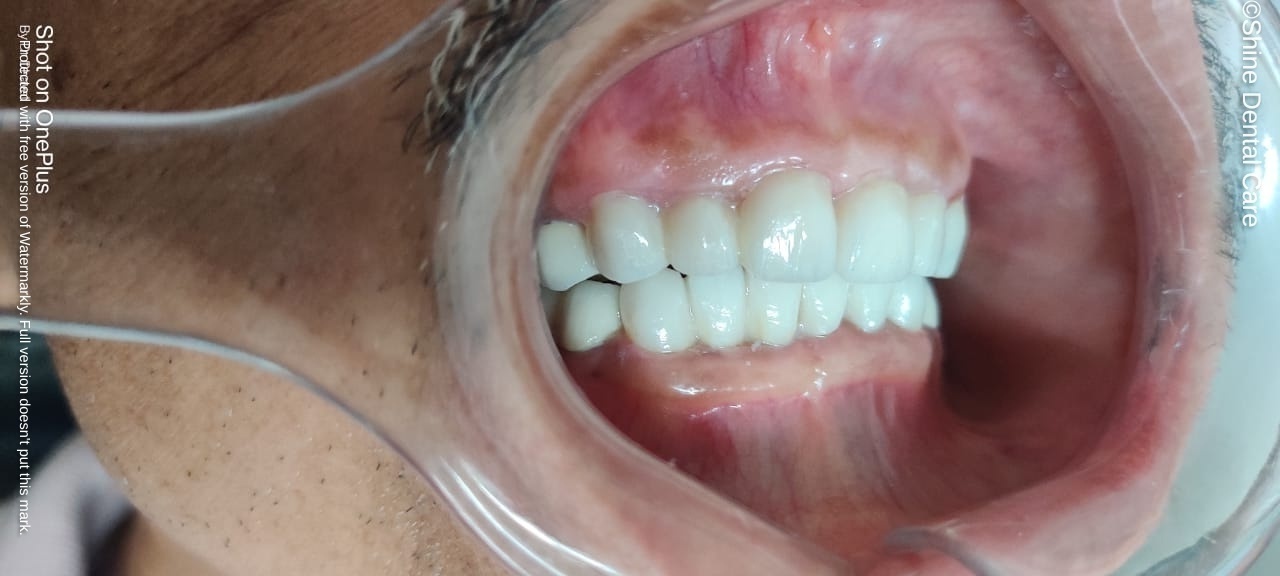

Full Mouth Rehabilitation

As the name implies, Full Mouth Rehabilitation refers to rebuilding and/or replacing all of the teeth ina patient’s mouth. Full Mouth Rehabilitations combine esthetics with the science of restorative dentistry to improve the health, function, and beauty of the mouth.

The treatments can include onlays, crowns, bridges, veneers, dental implants, and/or dentures that will essentially provide not only a "'smile makeover", but improved chewing efficiency for the patient. In some patients, other specialties will orthodontics may also be employed to facilitate the best possible outcome.